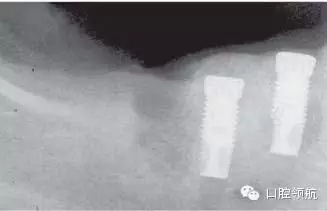

皮質(zhì)類固醇是一種可治療多種系統(tǒng)性疾病的常見(jiàn)藥物。長(zhǎng)期使用這類藥物可抑制患者免疫反應(yīng),使他們更易遭受細(xì)菌、病毒及真菌的感染。這些感染采用常規(guī)治療很難奏效,而且服用外源激素類藥物的患者有患骨質(zhì)減少、骨質(zhì)疏松癥的風(fēng)險(xiǎn)。臨床醫(yī)生檢查上下頜骨時(shí)應(yīng)事先知道有沒(méi)有這類情況(圖2.8a,b)。

圖2.8 (a,b)長(zhǎng)期服用皮質(zhì)類固醇的患者,種植4個(gè)月后失敗。